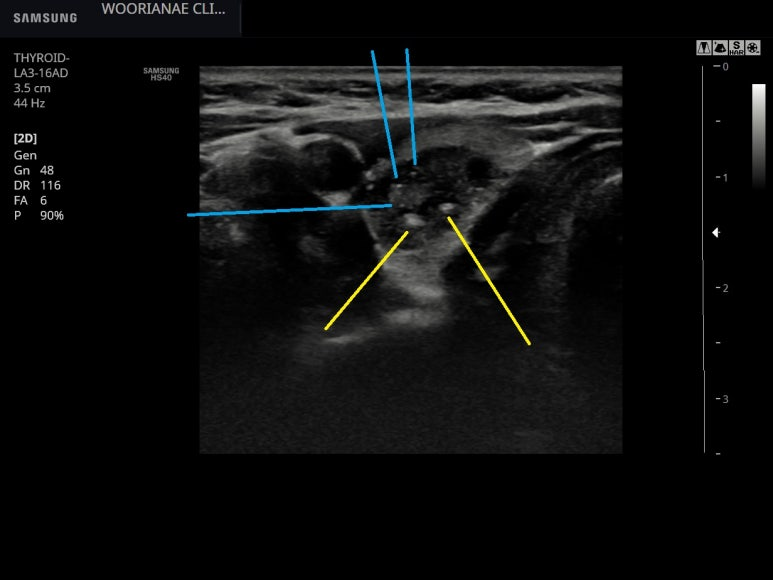

초음파 다시 시행, 아주 저음영이지 않고, 불균질한 (heterogenous) 한 모습

양성의 과증상 (hyperplasia) 로 생각이 되며, TIRAD는 3점 정도... 크기 기준에서 배제를 위한 FNA는 해볼수 있겠다고 설명함

결절의 상부에는 colloid particle로 봐도?

;;; 조직결과 이후 다시 보면 노란부분은 크기가 큰 편이며 microcalcification으로 봐도 될듯

장경은 3.65 cm로 대부분은 고형결절이며 일부 작은 부분만 낭성 변화가 있으며 주로 colloid particle이 있는 양성 소견으로 보았다.

일부 낭성변화가 있으며 미세석회화가 국소적으로 있는데...

; 갑상선 결절, 전형적인 유두암 소견은 아닌거 같으나... 세침 병리의 소견 --> 일부 낭성변화를 동반한 결절+미세석회화